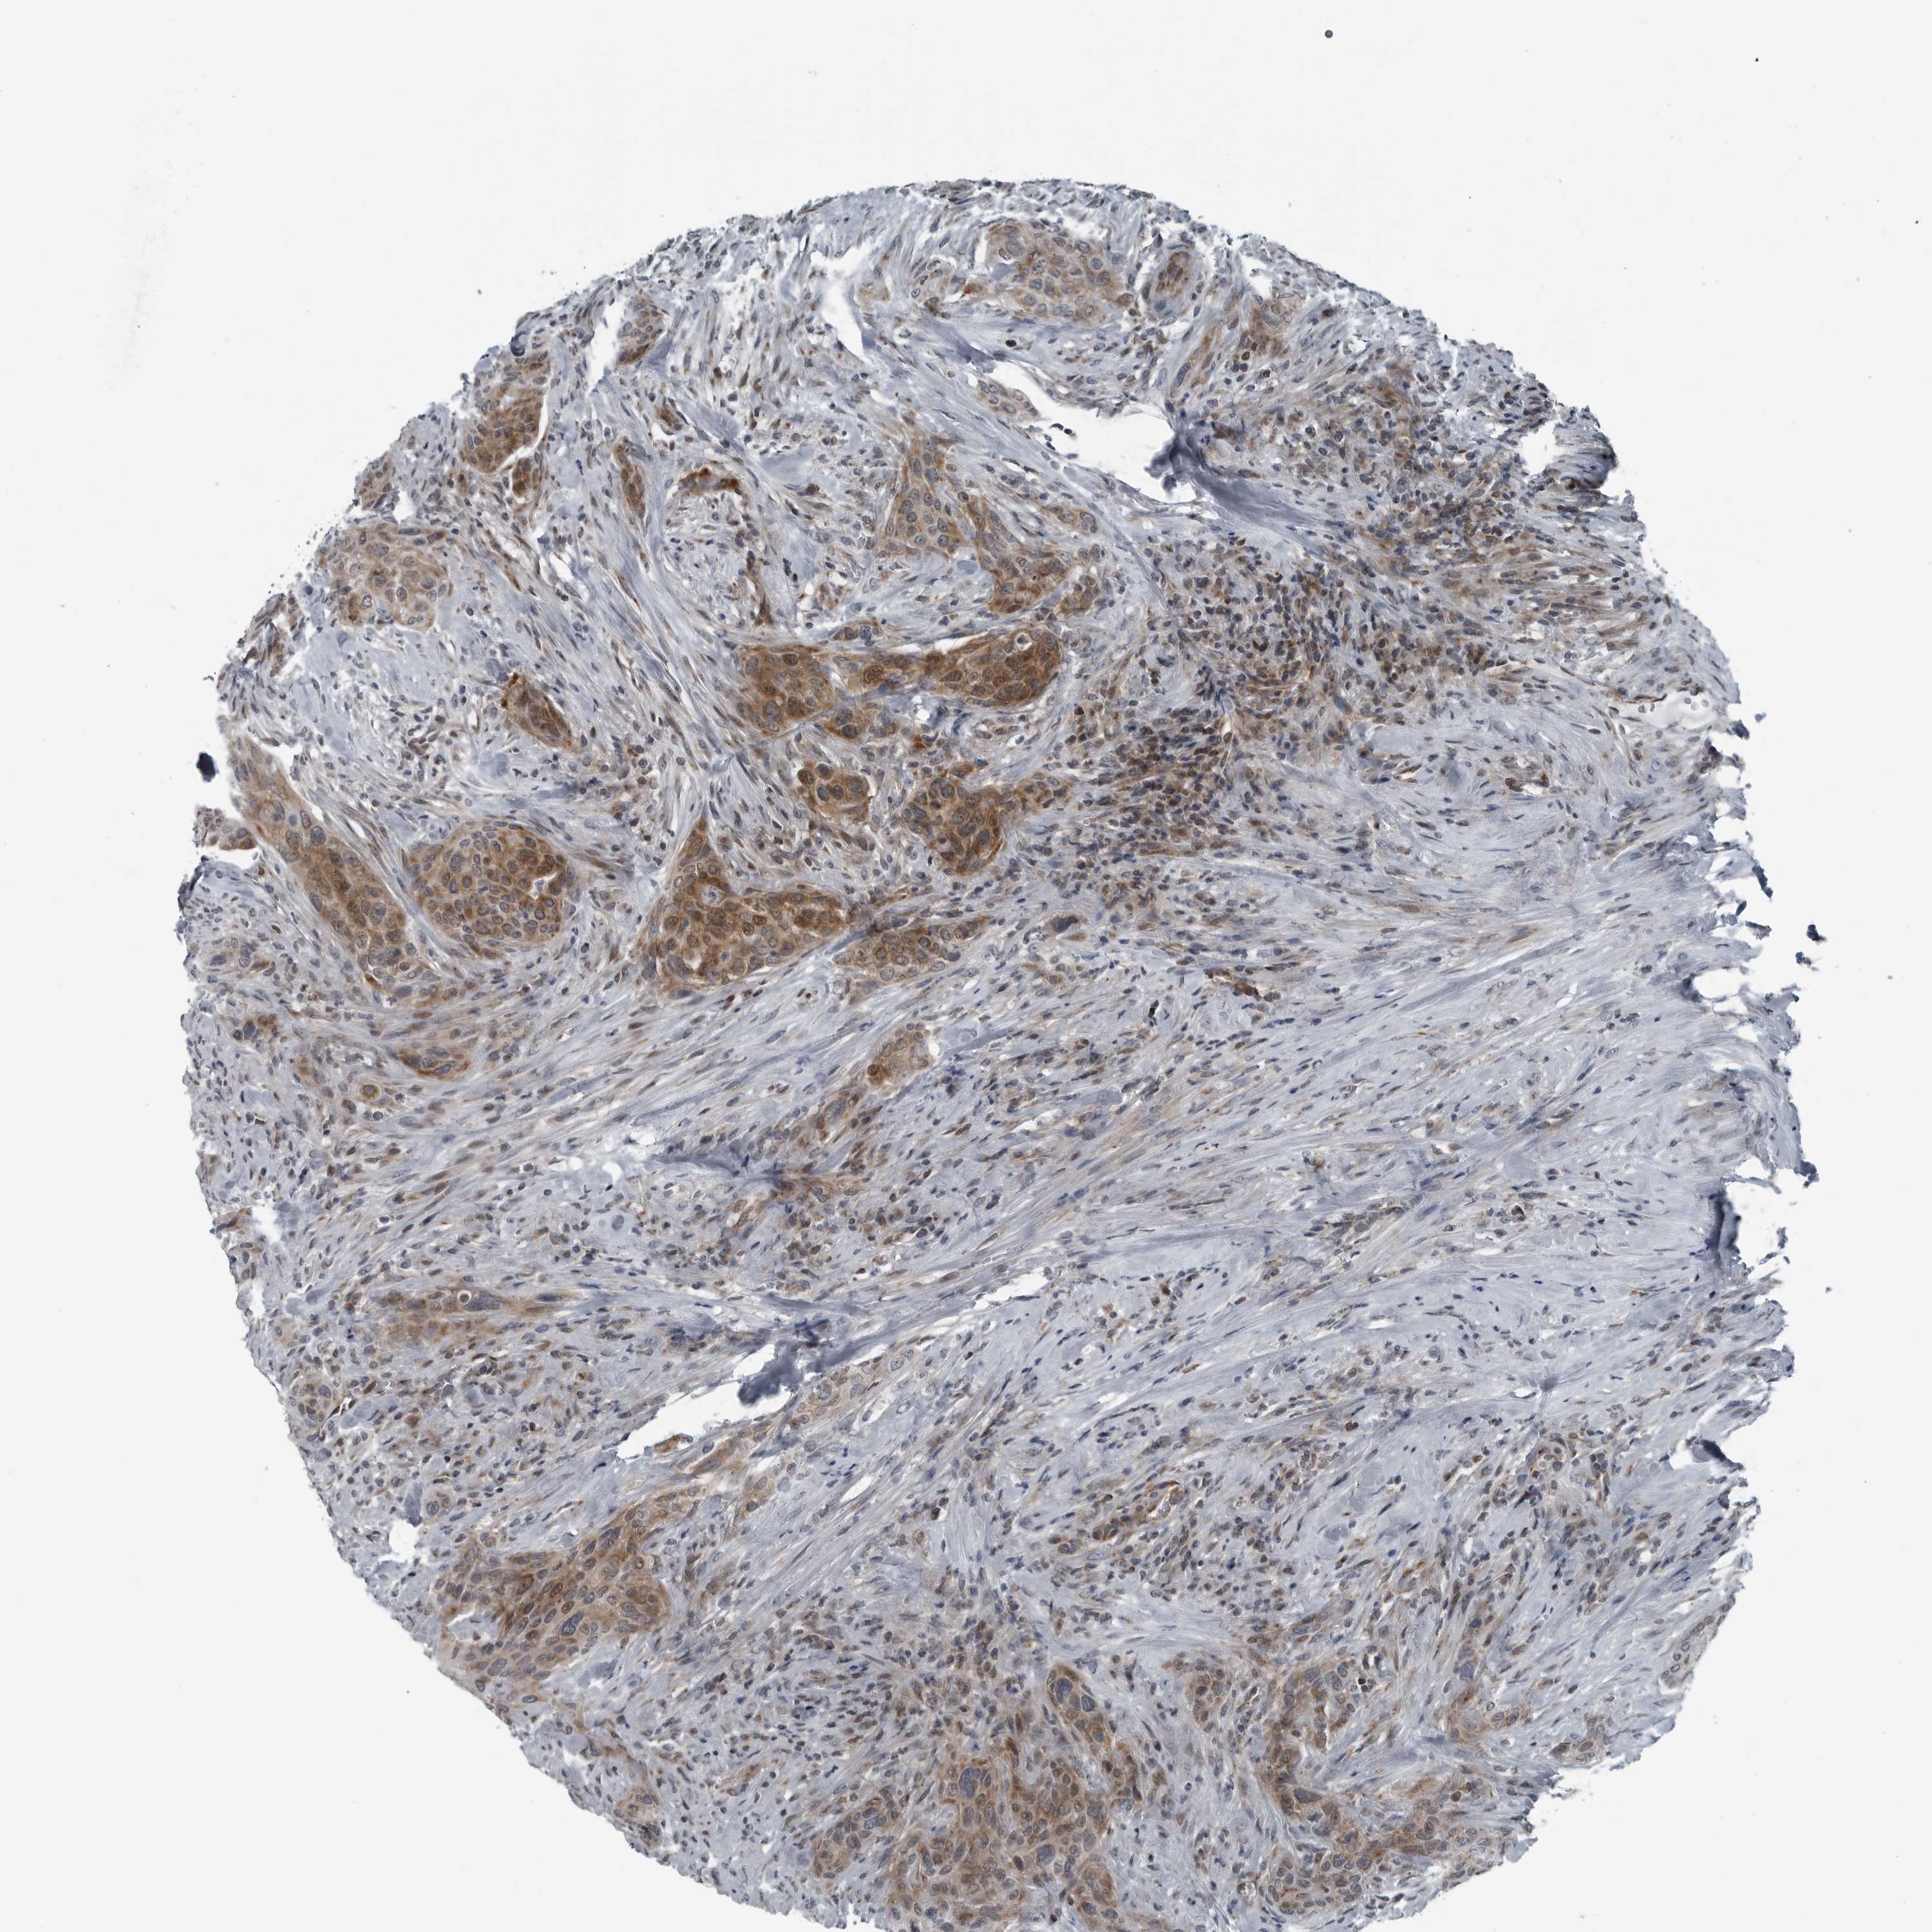

UROTHELIAL CANCER - Protein expressioni

A mouse-over function shows sample information and annotation data. Click on an image to view it in a full screen mode. Samples can be filtered based on level of antibody staining by selecting one or several of the following categories: high, medium, low and not detected. The assay and annotation is described here.

Note that samples used for immunohistochemistry by the Human Protein Atlas do not correspond to samples in the TCGA dataset.

Antibody stainingi

Antibody staining in the annotated cell types in the current human tissue is reported as not detected, low, medium, or high, based on conventional immunohistochemistry profiling in selected tissues. This score is based on the combination of the staining intensity and fraction of stained cells.

Each image is clickable and will lead to virtual microscopy that enables deeper exploration of all samples and also displays staining intensity scores, fraction scores and subcellular localization as well as patient and tissue information for each sample.

Antibody HPA027405

Antibody HPA027459

Antibody HPA027463

Staining

High

Medium

Low

Not detected

Intensity

Strong

Moderate

Weak

Negative

Quantity

>75%

75%-25%

<25%

None

Location

Nuclear

Cytoplasmic/membranous

Cytoplasmic/membranous,nuclear

Urothelial carcinoma, Low grade

Urothelial carcinoma, High grade